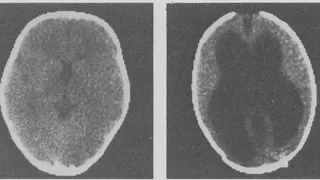

Is your brain really necessary is documentaire over de aandoening ‘hydrocephalus’, beter bekend als waterhoofd.